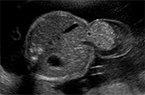

Grossesse triple, triamniotique trichoriale de 5 SA Grossesse triple, triamniotique trichoriale de 5 SA Grossesse triple, triamniotique trichoriale de 5 SA